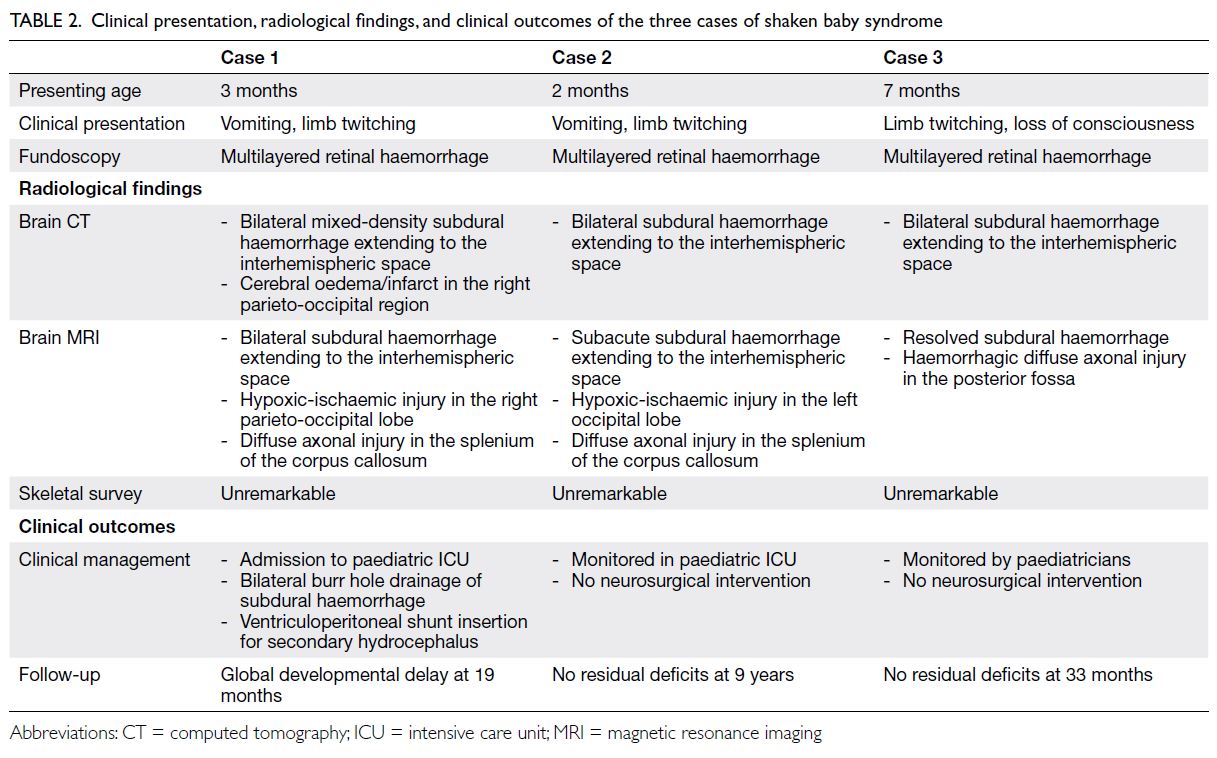

Computed tomography (CT) was the

showed positive findings. Three cases (12.5%)

(n=1), prompting further evaluation by MRI. Shaken

(n=2) [Fig 4]. These patients, aged between 2 and

7 months, presented with non-specific symptoms

such as seizures (n=3), vomiting (n=2), and loss of

consciousness (n=1). Fundoscopic examination

confirmed multilayered retinal haemorrhages in all three cases, whereas skeletal surveys were

unremarkable (Table 2). The remaining two CT-positive

Table 2. Clinical presentation, radiological findings, and clinical outcomes of the three cases of shaken baby syndrome

Two patients with severe abusive head

trauma required admission to the paediatric

intensive care unit. One of these patients warranted

multiple neurosurgical interventions, including

bilateral burr hole drainage and placement of a

ventriculoperitoneal shunt. The remaining two cases

of abusive head trauma were managed conservatively.

At the most recent follow-up, one patient—the most severely affected—demonstrated gross motor delay

at 19 months of age. All other patients showed no

neurological deficits or developmental delay to date.